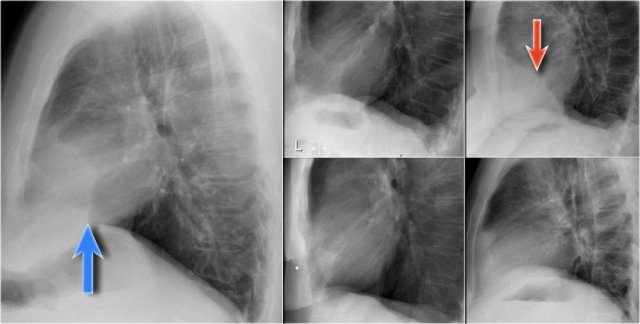

On this lateral film there is too much density over the lower part of the spine.

First study the lateral film and decide on which side the pathology is located.

By only looking at the interfaces of the left and right diaphragm on the lateral film, it is possible to tell on which side the pathology is located.

In this case we cannot follow the contour of the right diaphragm all the way to posterior, which indicates that there is something of water-density in the right lower lobe.

Continue with the PA-film of the same patient...

On the PA-film there is a normal silhouette of the right heart border, so the pathology is not in the anterior part of the chest, which we already had decided by studying the lateral view.

Question:

Why do we still see the silhouette of the right diaphragm on the PA-film?

Answer:

What we see is actually the highest point of the right diaphragm, which is anterior to the pneumonia in the right lower lobe.

The pneumonia does not border the highest point of the right diaphragm and there will be no silhouette sign.